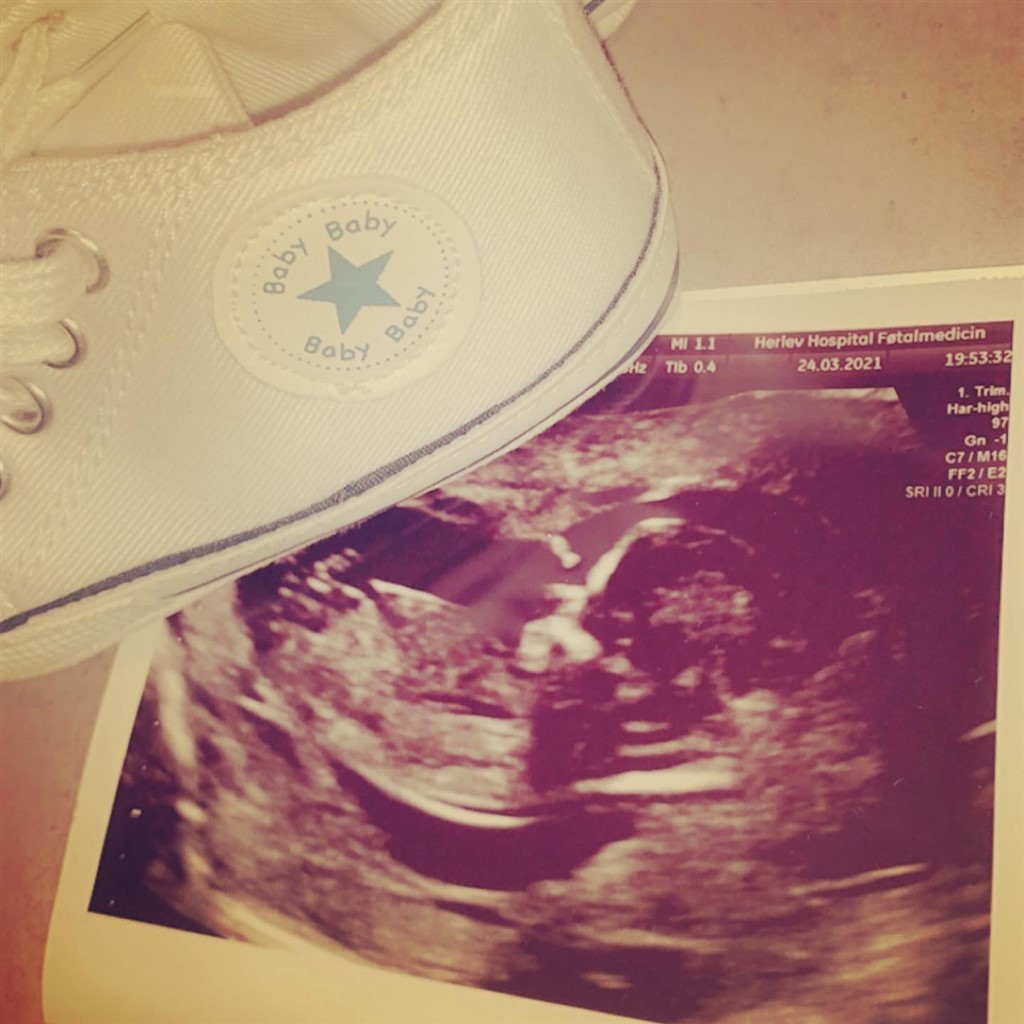

Nub teori ??

hvad vil i sige ?? Nogen det vil komme meg et bud

Dwt er meget svært at se på de billeder. Men et forsigtigt gæt vil være en pige

Pige... Forsigtigt gæt